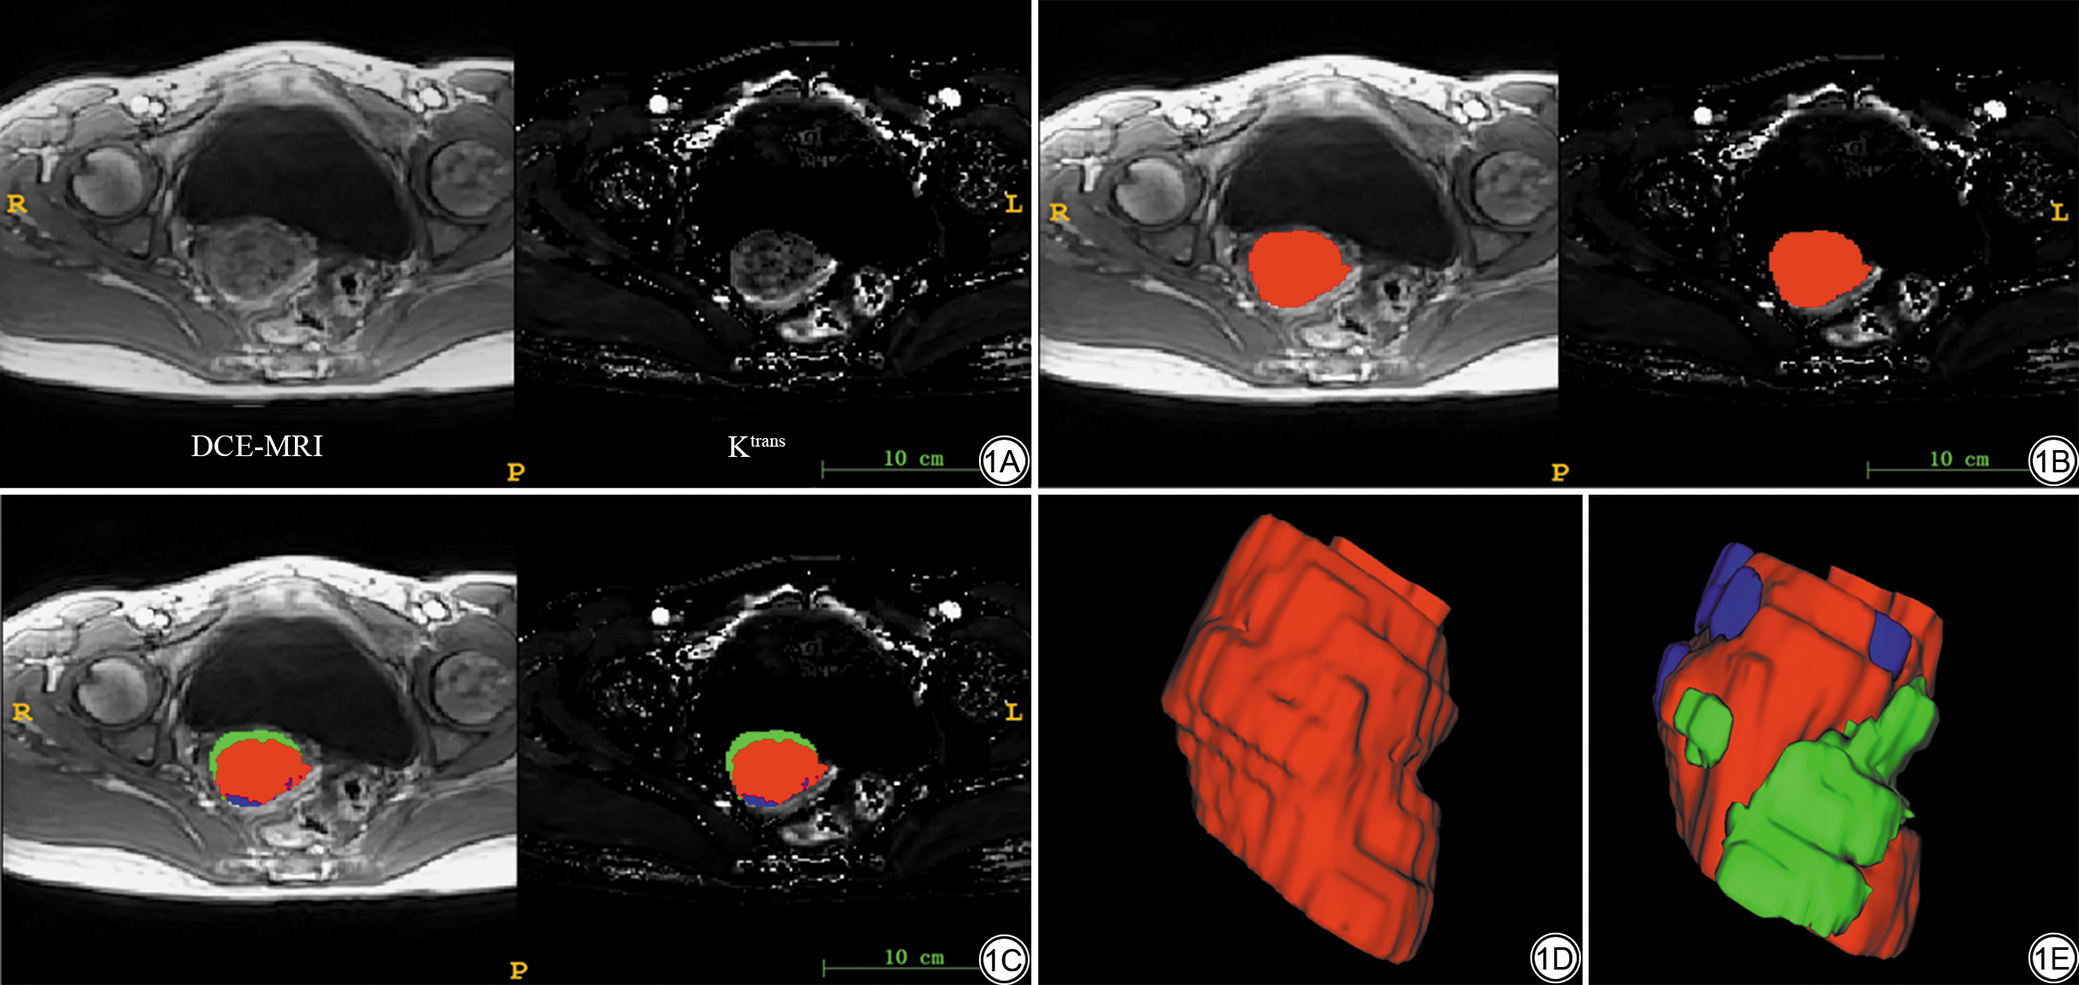

DCE-MRI数据处理采用Extended Tofts Linear双室模型,首先按顺序导入2°和15°翻转角数据,将DCE-MRI序列35期图像调入Syngo后处理工作站,应用Tissue4D由髂内动脉的时间-信号强度曲线(time-intensity curve, TIC)确定血流峰值期,获得转运常数(volume transport constant, Ktrans)定量参数图以及分别测量全肿瘤最大层面的Ktrans、速率常数(rate constant, Kep)、血管外细胞外间隙容积分数(extravascular extracellular volume fraction, Ve)的均值。由于成像技术的差异,来自不同机器的图像可能具有不同的像素值。为了减轻异常值的影响,我们对所有图像进行了标准化。使用空间标准化来减少体素间距的变化,在我们的实验中采用了固定分辨率重采样(1.0 mm×1.0 mm×3.5 mm)方法来解决这些问题,之后对图像标准化处理;在DCE-MRI根据TIC选取峰值期期相图像,将Ktrans定量参数图像配准到35期时相峰值期图像中,在峰值期图像中进行人工分割,图像分割在ITK-SNAP软件(3.8.0,http://www.itksnap.org)进行。每例患者的ROI都是由一名有10年工作经验的影像科医生(主治医师)逐层勾画(图1)。采用组内相关系数(intra-class correlation coefficient, ICC)评估观察者内部和观察者间的重复性。随机选择21例患者,由具有15年经验的影像科医生(副主任医师)重新进行分割,以衡量观察者间的可变性。这2位影像科医生对于临床病史和术后病理不知情。对提取的放射组学特征进行一致性评估,ICC>0.75认为一致性较好。

图1  基于DCE-MRI图像沿病灶边缘逐层勾画三维VOI示意图。1A:DCE-MRI图像及配准后的Ktrans参数图;1B:肿瘤感兴趣区(红色);1C:肿瘤生境区域感兴趣区;1D:肿瘤VOI;1E:肿瘤生境区域VOI。DCE-MRI:动态对比增强磁共振成像;VOI:容积感兴趣区;Ktrans:转运常数。

Fig. 1  Schematic illustration of three-dimensional VOI delineation along lesion margins on DCE-MRI images. 1A: DCE-MRI and co-registered Ktrans parametric maps; 1B: Tumor region of interest (red contour); 1C: Tumor habitat region of interest; 1D: Whole-tumor VOI; 1E: Habitat subregion VOI. DCE-MRI: dynamic contrast-enhanced magnetic resonance imaging; VOI: volume of interest; Ktrans: volume transport constant.